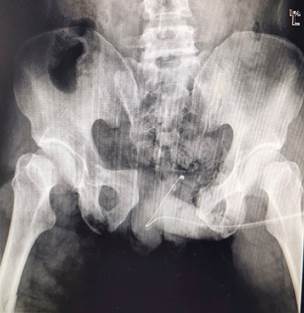

患者男性,42岁,入院前8小时被机器绞伤,伤后患者全身多处疼痛活动受限。急诊入院诊断为失血性休克、骨盆骨折、胫腓骨开放性骨折(右)、股骨干骨折(右)、下肢肌腱断裂(右小腿前方肌腱)、会阴开放性损伤、腹部损伤、足背动脉断裂(右)、肛门直肠损伤、阴囊开放伤,病情极为危重。

普外科对患者行腹部造瘘术,泌尿外科行会阴部清创缝合术,都顺利完成,创伤骨科团队在外科腹部造漏术的同时,就迅速利用微创技术完成了骨盆前环的外架置入,接下来以最快的速度复位了骨盆前后环,固定了外架并启动了导航系统,术中导航系统影像分析进一步证实了患者的骶骨严重变异,且手术安全区很小,风险极高。经过手术医生仔细而迅速的规划和与导航技师的默契配合,应用机器人导航技术,后环骶髂螺钉快速而准确的被植入并有效的固定了骨盆后环,从规划到顺利完成置钉,整个过程仅用了20余分钟,机器人导航技术同传统手术相比大大降低了手术时间,患者的生命得救了。

由于是急诊抢救手术,术前准备时间非常有限,也无法进行充分的肠道准备,并且在短暂的术前计划中,手术医生发现患者为一例不多见的骶骨严重变异患者,即便择期手术也有很大的手术风险,但骶髂关节损伤如果不进行紧急处理,无法有效控制出血,也就无法及时有效的抢救患者生命。幸运的是我院创伤骨科已在国内率先开展了机器人导航辅助技术,对于该类患者不但明显的提高了手术治疗效果,而且最大限度的降低了术中的并发症。